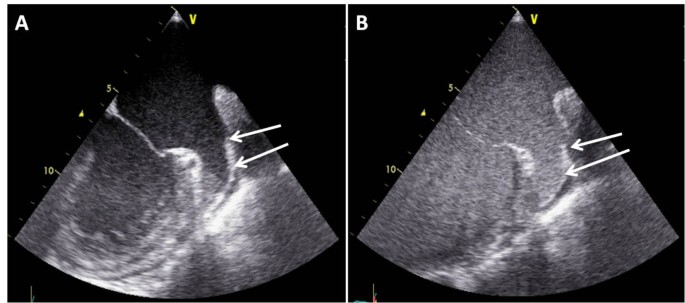

Cineloops of the multiplane examination of the LA and LAA were digitally recorded (Philips IE33, GE Vivid VII) throughout each imaging method. Blood flow velocities of the atrial appendage were measured by pulsed wave doppler echocardiography. For the purpose of the present investigation, in group 1 echocardiographic images were acquired before and after bolus application of 1ml contrast agent (SonoVue™ Bracco Diagnostics Inc., Princeton, NJ, USA) into an antecubital vein followed by a bolus of 5-10ml saline according to our standardized study protocol. To avoid shadowing or swirling artefacts, the timing of image acquisition, mechanical index and the setting of the focus zone were individually optimised. Figure 1 depicts examples of native and contrast enhanced TEE.

In group 1, the definite existence of a thrombus (classification 1) was assumed in 14 (15.6%) patients during initial examination without contrast enhancement and in 10 (11.1%) patients after the contrast agent was applied (Figure 2). Of the 14 patients with thrombus detection at native imaging, 8 were confirmed by contrast enhanced TEE, 2 remained unclear and in 4 patients a thrombus could be safely excluded and CV performed without subsequent complications. Contrast enhancement allowed for the additional identification of 2 patients with thrombi, in whom native imaging yielded non distinctive findings.

Contrast enhanced TEE permitted the exclusion of thrombi in 4 patients, in whom thrombi were suspected during native imaging. This can be explained by the capability of the contrast agent to completely opacify the LAA even in the presence of artefacts during native imaging leading to falsely identification of thrombi [4]. In 2 patients (2.2%) the contrast application allowed for the additional delineation of atrial thrombi and suspension of the scheduled CV. In these cases, native TEE was not able to detect the atrial thrombi due to insufficient image quality and low degree of echogenicity of the thrombotic material, whereas a persisting contrast-free area in the tip of the LAA during contrast enhanced imaging indicated the presence of a thrombus. In accordance with the results of Recke et al. [4] the number of not conclusive TEE decreased significantly (5.6% vs. 17.8%) using contrast enhancement and therefore facilitated decision making for or against CV.